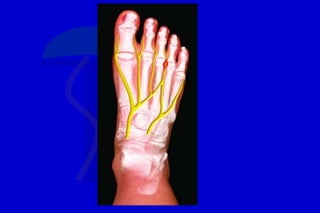

Durante la marcha, después del choque del

talón, el centro de presión se mueve muy

rápidamente hacia el área de las cabezas

metatarsianas, y allí permanece alrededor

del 50% de la fase de apoyo, después de la

cual se desplaza hacia los dedos

Debido a este extenso período de apoyo en el área

metatarsiana un alineamiento anormal del antepié

localizado o generalizado generará cargas

desiguales sobre los metatarsianos y determinará

una metatarsalgia